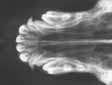

| Vom

Wellensittich bis zum Bernhardiner - vom Zahn bis zur Hüfte

können und müssen scharfe

und kontrastreiche

"Standbilder" angefertigt werden. |